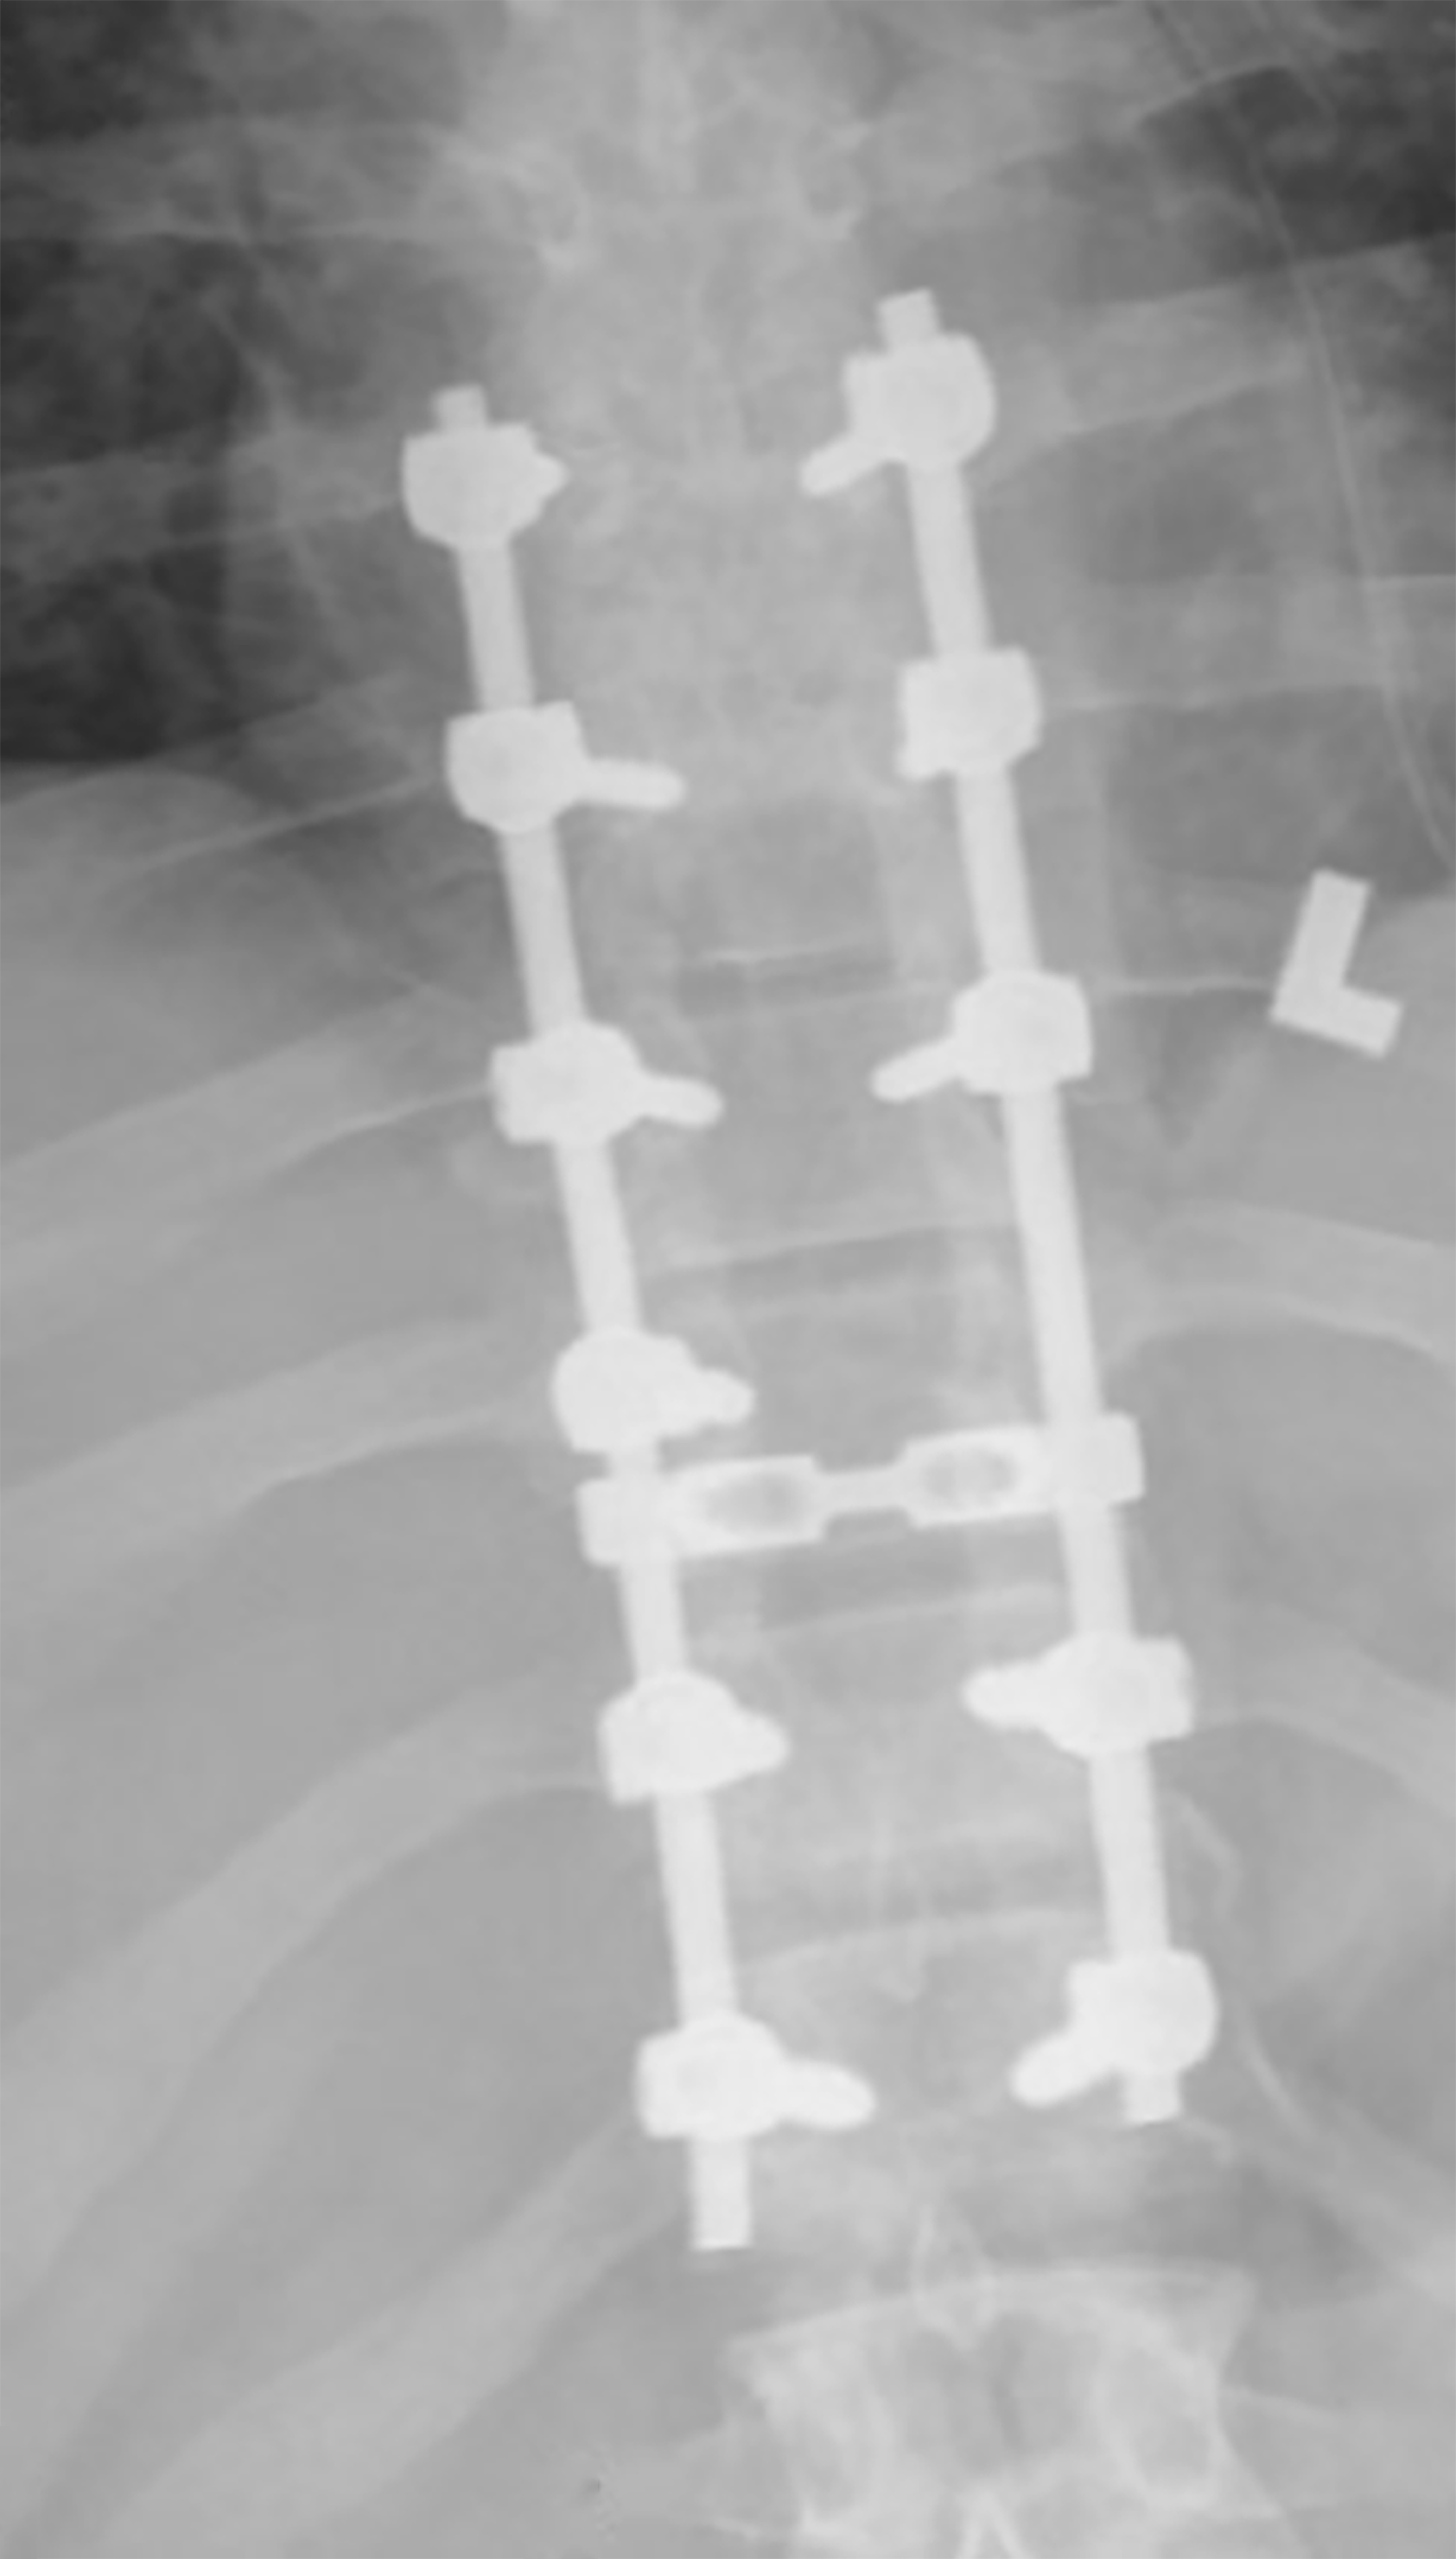

Spinal Fusion Anterior - Posterior

- The picture shows the thoracic pedicle screws and rods used for stabilization